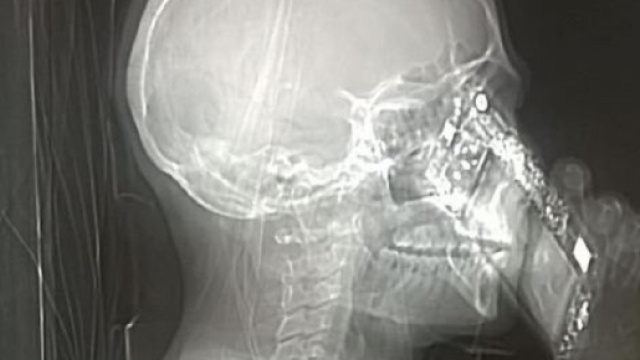

Tac compromessa da un cellulare? ecco l'assurda foto

Pochi giorni fa, al Cardarelli di Napoli, si è presentata una signora che lamentava dei forti e continui mal di testa. Dopo molti accertamenti e con il sospetto che la donna soffrisse di cefalea, i medici hanno preso la decisione di sottoporla ad una Tac. La procedura di routine dell'esame tomografico è nota quasi a tutti: bisogna togliere ogni tipo di oggetto metallico o simili (collane, orecchini, piercing, telefoni ecc.) per evitare che questi compromettano l'immagine risultante dalla Tomografia. La cosa che, al contrario, ha lasciato basiti i medici dell'ospedale napoletano è stata che la donna abbia deciso di rispondere al proprio telefonino, compromettendo la foto registrata dalla tac.

Infine, i medici hanno deciso di diffondere la foto della tac per chiarire quanto il comportamento della signora possa essere sbagliato e pericoloso. Lo stesso primario Mario Muto ha dichiarato, a Tgcom, che la situazione sembrava davvero paradossale e che i tecnici hanno provveduto ad interrompere subito l'esame.